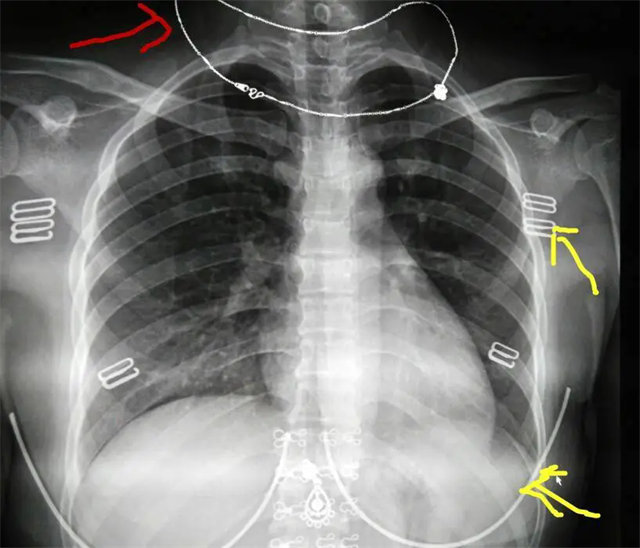

缺陷:左肩胛骨部分与左肺野重叠。

解决:使患者左肩旋前紧贴成像件重新曝光。